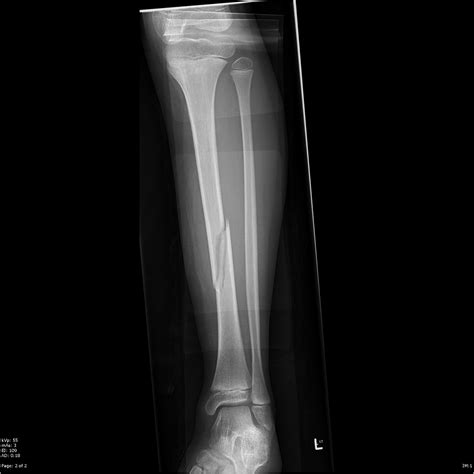

A transverse fracture is characterized by a break that runs perpendicular to the long axis of the bone. This type of fracture is often the result of a direct, high-impact force applied to the bone. Common causes include:

Transverse fractures can occur in any bone but are most commonly seen in the long bones of the arms and legs, such as the femur, tibia, and humerus.

• Imaging Studies: X-rays are the primary imaging tool used to confirm the diagnosis. They provide a clear view of the bone and the fracture pattern.

It is important to note that the transverse fracture definition helps in differentiating this type of fracture from others, such as oblique or spiral fractures, which have different patterns and treatment approaches.